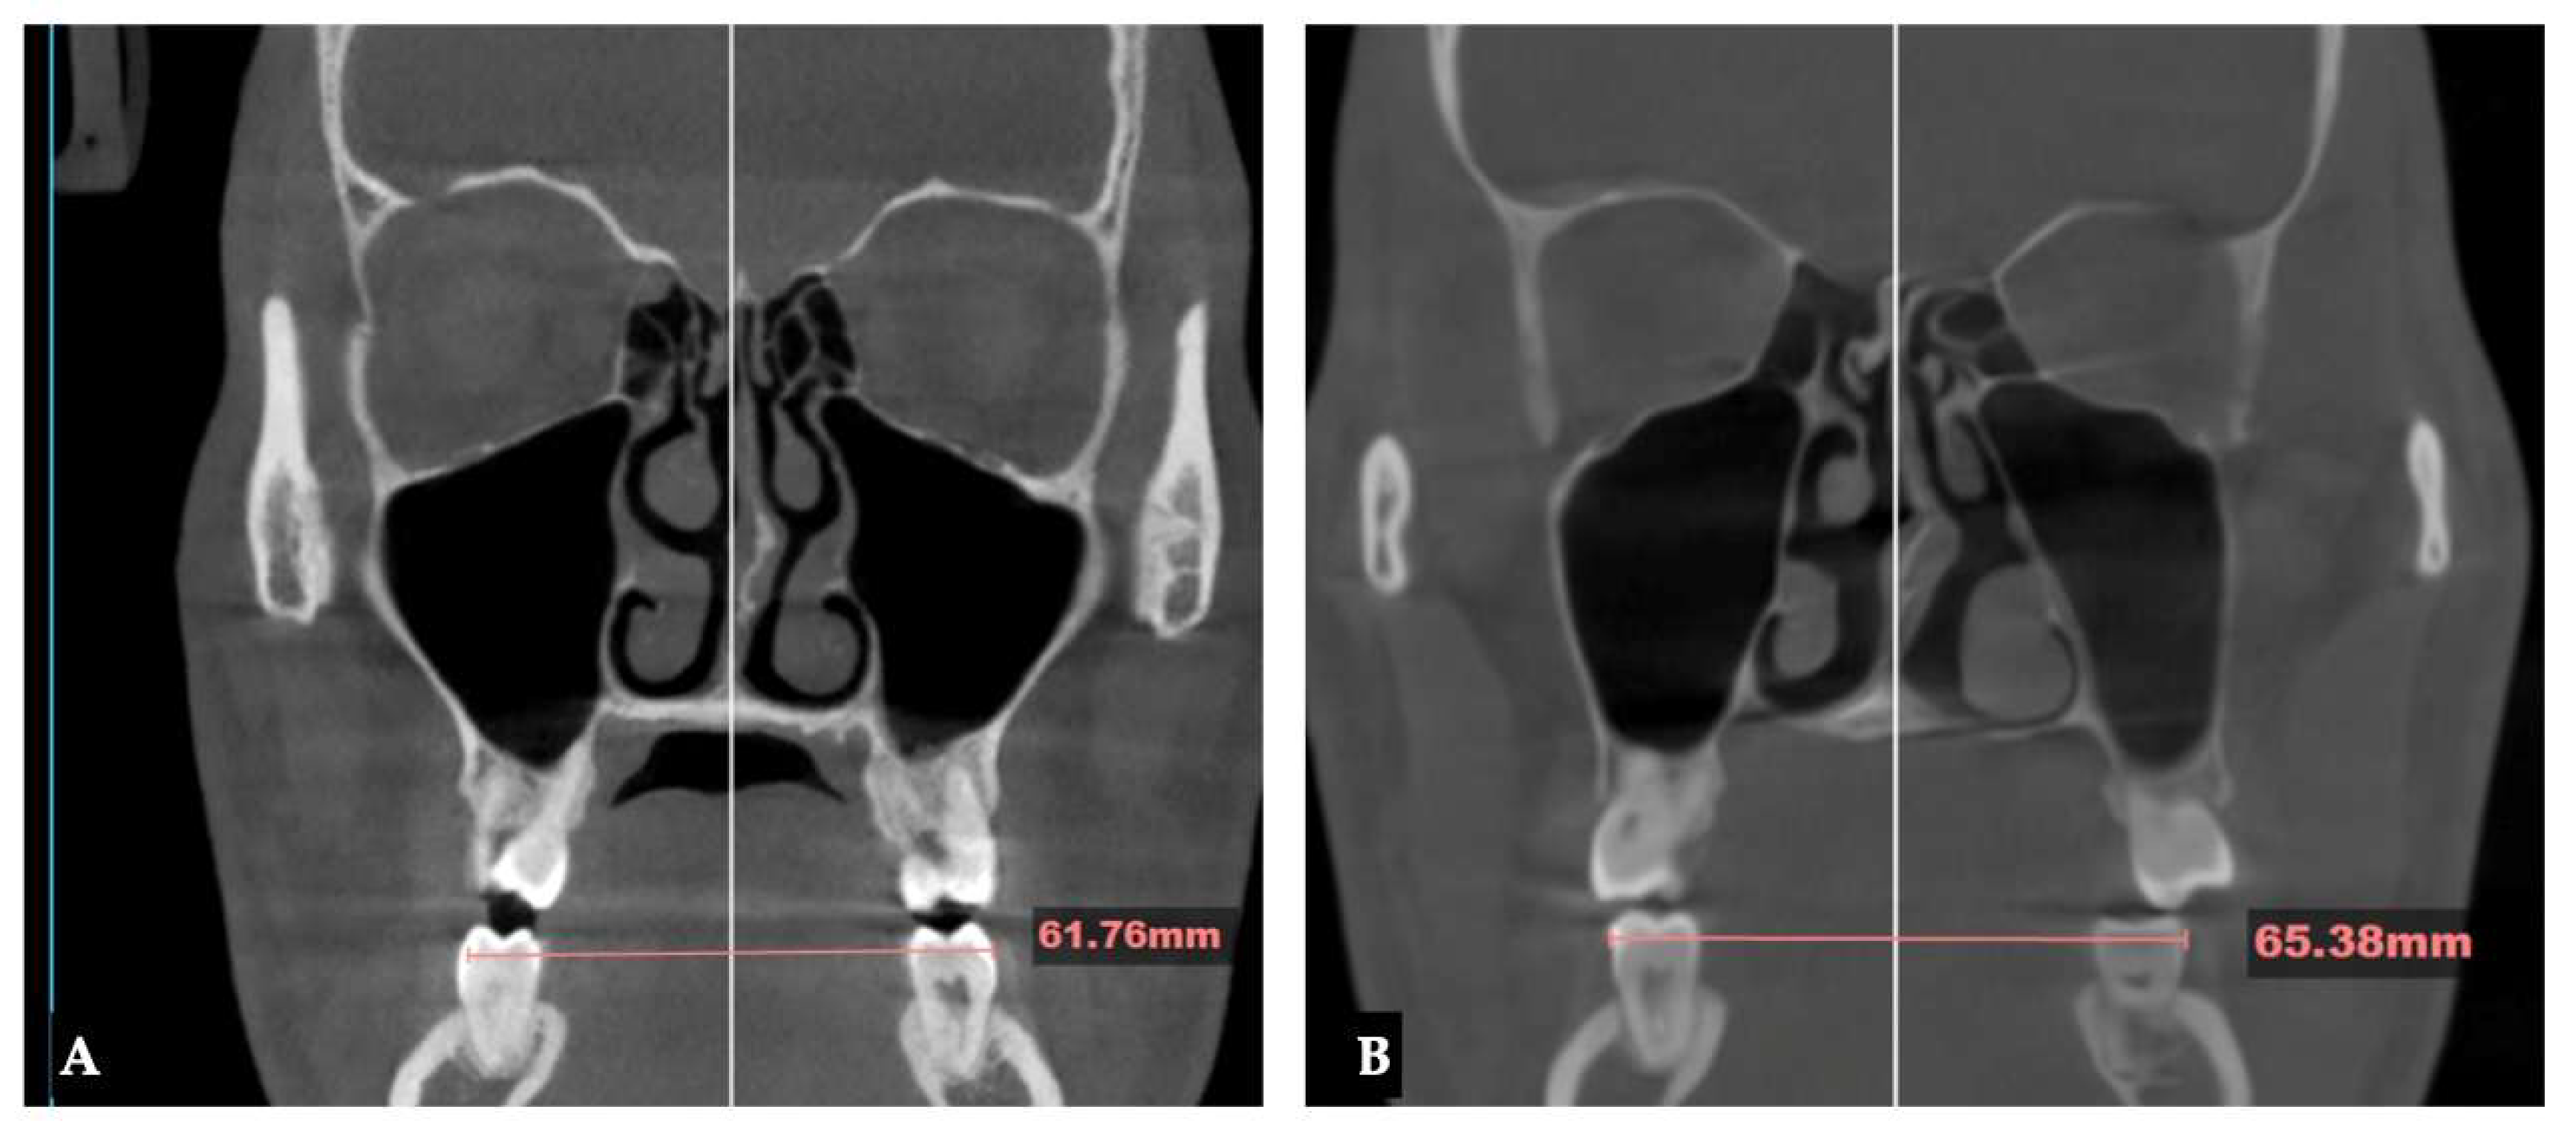

Background: While mini-screw-assisted rapid palatal expansion (MARPE) is effective for correcting maxillary transverse deficiency in adults, perimaxillary suture disarticulation—particularly at the pterygomaxillary junction—can be inconsistent. This study evaluates skeletal and dentoalveolar outcomes of a novel 3D-guided midpalatal piezocorticotomy-assisted MARPE protocol, focusing on expansion symmetry and pre-existing asymmetries. Methods: Three adult patients were retrospectively analyzed after treatment with 3D-guided midpalatal piezocorticotomy-assisted MARPE expansion and one with non-guided midpapalatal piezocorticotomy and MARPE expansion. Surgical guides were digitally designed using CBCT data to align with the nasal septum orientation in multiple planes. Perimaxillary suture disarticulation was measured pre- and post-expansion, and dentoalveolar changes were evaluated. Post-expansion asymmetries were addressed using directly printed aligners. Results: Complete midpalatal suture separation (mean 8.48 mm), involving both anterior and posterior nasal spine regions, was achieved in one patient. Bilateral pterygomaxillary disarticulation averaged 1.06–1.23 mm, resulting in forward–outward rotation of the nasomaxillary complex. Additional separation occurred at the frontonasal (2.03 mm) and vomeromaxillary (1–2 mm) sutures, with no significant changes in orbital or peri-orbital sutures. One patient presented with pre-existing dentoalveolar asymmetry, which intensified the perceived post-expansion imbalance but was successfully corrected with directly printed aligners. In the second case, 5.6 mm of suture separation resulted in a limited lateral nasal width increase (<1.5 mm), while maxillary base expansion exceeded 6 mm. A significant canine plane cant (1.2 mm) and divergent axial inclinations of the maxillary central incisors relative to the palatal plane were also observed. In the second case, a non-impactful palatal bone fracture with asymmetric displacement of the left palatine fragment was documented. After 16 months of aligner therapy, all cases exhibited favorable remodeling of the palatal structures, midpalatal suture, and alveolar processes, accompanied by improved dental alignment, occlusal plane symmetry, and mandibular dentoalveolar adaptation. The dento-alveolar expansion achieved in the third case over the course of 16 months of treatment was approximated at 4 mm. The fourth case showed consistent improvement with direct printed aligners after MARPE midpalatal diasrticulation of 11 mm after experiencing minor bone fracture. Conclusions: Human skulls exhibit considerable variability between the left and right sides, which can influence spatial balance. Pre-existing cranial asymmetries appear to be the primary contributors to asymmetry following MARPE treatment. Careful evaluation of dentoalveolar discrepancies and axial tooth inclinations is essential for preventing and managing potential asymmetric dental arch outcomes during the post-expansion phase. Although peri-maxillary bone fractures are relatively uncommon, their occurrence is influenced by multiple factors. Adjunctive techniques, such as 3D-guided midpalatal piezocorticotomy, show promise in significantly lowering the risk of intra-expansion peri-maxillary fractures.

| Parameter | Before Expansion | After Expansion |

|---|---|---|

| Maxillary canine plane | -1.2 L | -4.1 L |

| Mandibular canine plane | 0.3 R | -1.1 L |

| Chin cant | -0.9 L | -2.0 L |

| Body cant | -1.6 L | -3.8 L |

| Gonion cant | 0.2 R | -5.3 L |

| 2nd molar cant | -0.4 L | -0.4 L |